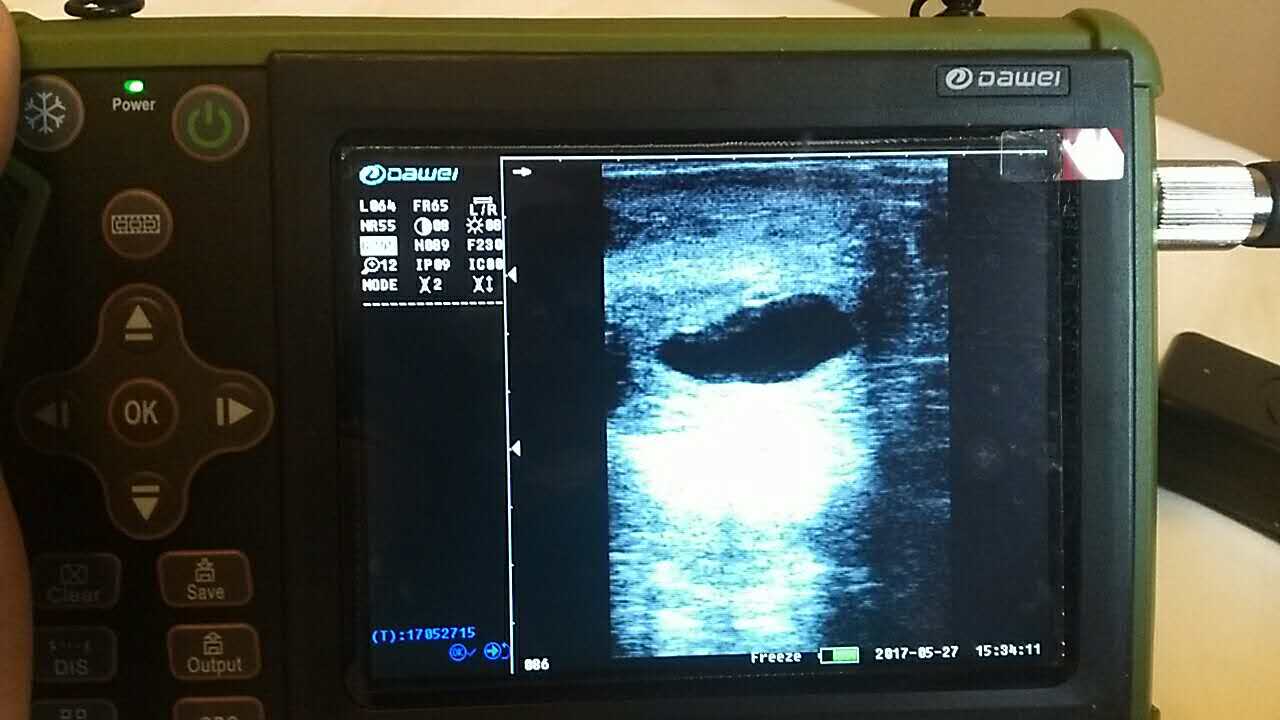

養(yǎng)殖基地140只生產母羊集體接受了B超檢查,利用現(xiàn)代化技術方法,解決生產母羊繁育難題促進畜牧業(yè)生產結構的調整。 在檢查中,技術人員拿著B超儀器,給生產母羊做免費受孕普查。用B超檢測母羊受孕情況,用這種方法給母羊做檢測可以準確掌握母羊是否受孕、母羊生產周期。通過B超早期孕檢和生殖系統(tǒng)疾病診斷,可以清晰的觀測到生產的宮腔和胎兒的生產發(fā)育情況。除了幫助基地對問題羊做出正確診斷,提出合理的治療方案,淘汰無治療價值的長期空懷羊,還能提高受孕率,降低飼養(yǎng)成本,有效規(guī)避了假妊娠造成的經濟損失。

檢測懷孕 估測胎仔數(shù) 疾病診斷 胎兒活力鑒定 胎心搏動 適用對象:適用于羊、豬、狗等動物受孕診斷(集成6種常見動物孕周測量數(shù)據(jù)包) 適用范圍:規(guī)?;i場,人工授精站,飼料/獸藥經銷商及企業(yè),科研教學單位 |